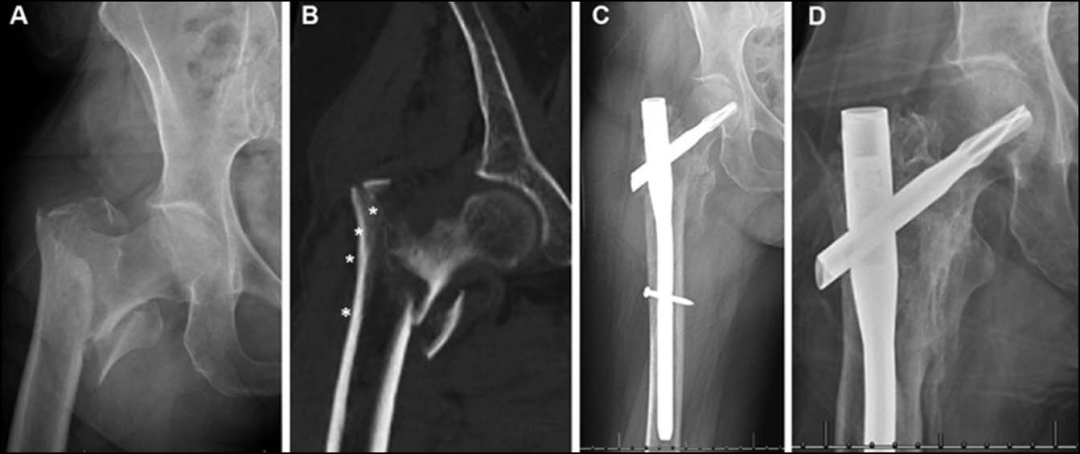

最常用的钉长是短钉(170~200mm)和长钉(300~480mm),(下图a短钉、c长钉)

短髓内钉手术时间短,远端锁定相对容易被广泛使用,短钉的缺点包括在髓腔宽或股骨近外侧皮质完整的患者中,可能发生钉子错位和随后的内翻塌陷,以及股骨近端骨干应力增加等。

长髓内钉更适合股骨髓腔宽、骨质疏松、病理性骨折、多次跌倒患者骨折、骨折伴近侧皮质缺损、转子间骨折延伸至小转子远端超过3cm。缺点,包括远端锁定困难、手术时间增加、扩孔需要增加、失血增加等。

。为了平衡短钉和长钉的优缺点,开发了中等长度的髓内钉(235和240mm):使用与短钉相同的远端锁定螺钉位置,但在锁定螺钉远端提供额外的钉子长度。